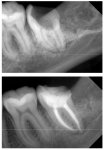

Снимки в 2д и делают прямо рядом, никуда ходить не надо и тоже на компе смотрят

>4) 3д снимок зубов, дохтор смотрит на компике твои гнелые пиньки

без визита никак. экстрасенсы в другом утреннике сидят. а так ты узнаешь об этом, когда завоешь посреди ночи от боли. особенно будет заебись, если ты в этот момент будешь где нибудь в командировке в ебенях, как было у меня. А вообще возьми яйца в руки и сходи сделай 3д снимок - стоит он хуйню, показывает вот прям вообще все, и абсолютно не больно. заодно йобастоматолог проконсультирует тебя, и скажет в какой дымоходе твои зуби или нет. Затянешь - выйдет больнее и дороже

Сейм. Мне 40, ходил к стоматологам хотя бы раз в год, но по ходу в какую-то пряник-клинику. Делали чистку, говорили что всё нормально с зубами. Осенью того года впервые пошёл в нормальную, и вот эти все чудеса увидел, кроме разме что ватки перед уколом. Там мне сделали КТ и оказалось что несколько зубов гниют сука изнутри. На сниках прямо видно что кариес в местах стыков зубов и тп. Сейчас хожу, лечу, уже несколько месяцев, стабильно им бабосики заношу. Ещё зубов 5 осталось долечить и возможно зубы мудрости удалить. Потом ещё буду элайнеры носить.

Ещё добавлю что кроме КТ мне фотографировали мои зубки фотиком и потом показывали на большом мониторе. Там каждую трещенку и пятнышко было видно.